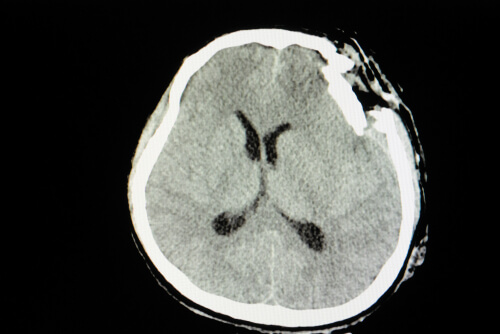

Un traumatismo craneoencefálico es una alteración neurológica fruto de un golpe violento. Así como podemos lastimarnos o fracturarnos un brazo en un evento desafortunado, también podemos dañar la base de nuestro sistema nervioso. La única diferencia es que dado el tipo de daño, las consecuencias serán mucho más graves.

El traumatismo craneoencefálico es una de las principales causas de muerte en el mundo. El daño de la estructura encefálica suele tener un desenlace mortal o dejar secuelas graves. Su incidencia está estrechamente ligada a nuestro estilo de vida. Es así que los accidentes automovilísticos son la principal causa entre los jóvenes y las caídas entre las personas mayores.

No es lo mismo una inflamación fruto de un golpe, que la pérdida de masa encefálica con fractura expuesta de cráneo. Igualmente, podemos decir que las principales secuelas se evidencian a nivel cognitivo, de memoria y de personalidad.